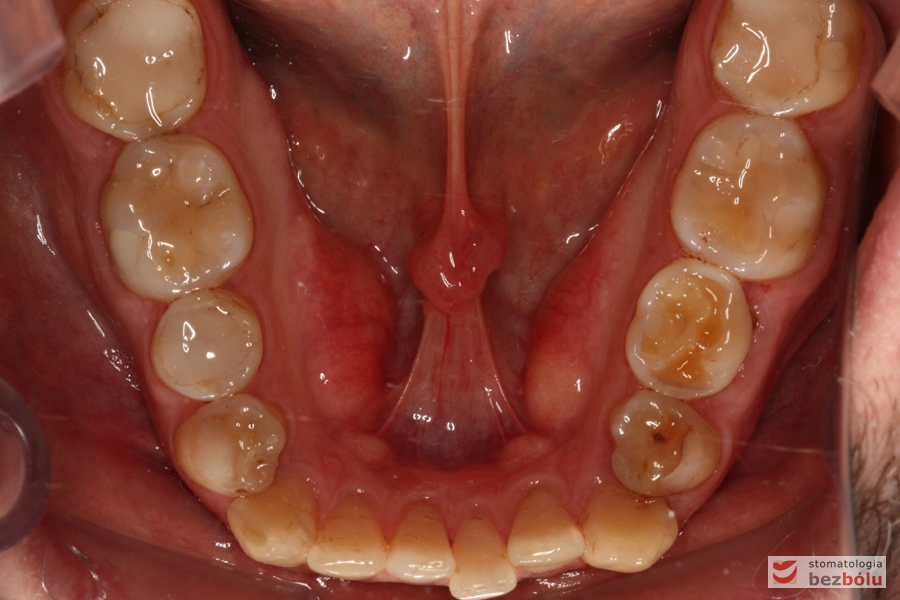

Żuchwa - widok okluzyjny, stłoczenia i rotacje w odcinku przednim, ząb mleczny po stronie lewej

Żuchwa – widok okluzyjny, stłoczenia i rotacje w odcinku przednim, ząb mleczny po stronie lewej